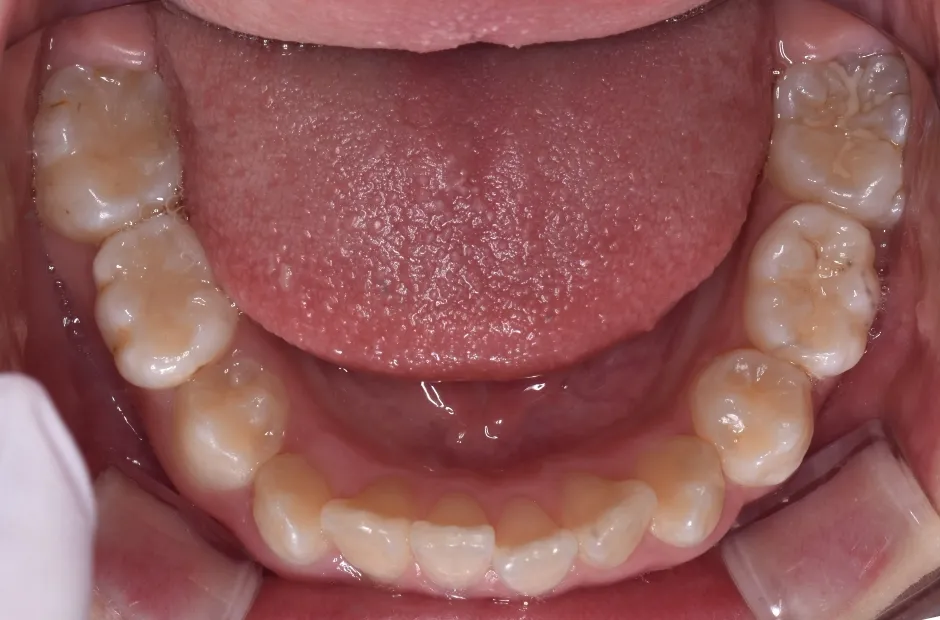

拡大床装置

叢生

| 診断名・主訴 | 叢生 |

|---|---|

| 年齢・性別 | 10歳・女性 |

| 治療期間・回数 | 2年半 |

| 治療に用いた主な装置 | 拡大床装置 |

| 抜歯部位 | なし |

| 治療費 | 30万円(税抜) |

| リスク・副作用 | 装置による違和感・疼痛・歯肉退縮・歯根吸収・虫歯のリスクなど |

治療前

治療中

治療後